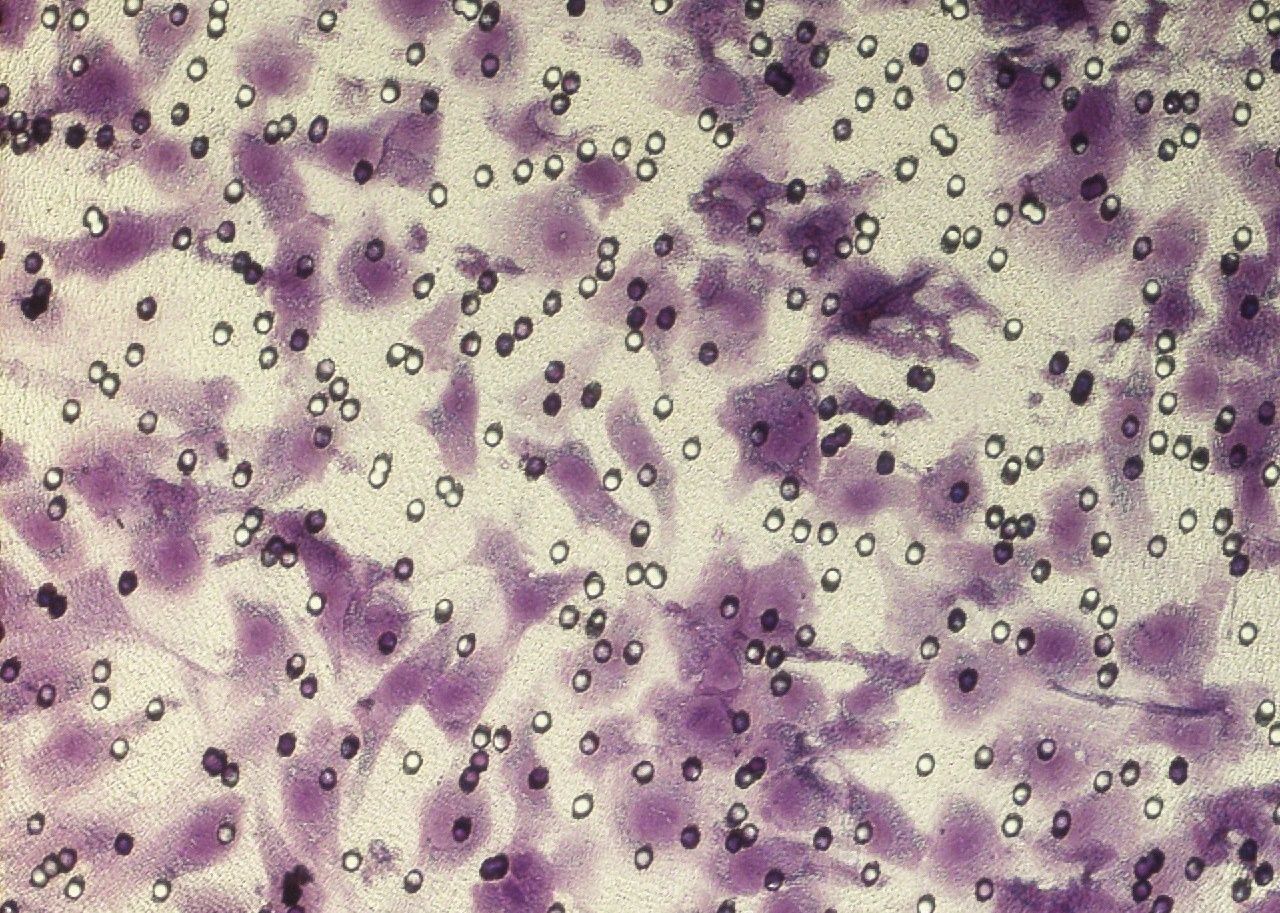

Transwell系統(tǒng)通過模擬細胞間的三維空間結構和微環(huán)境,為單層細胞屏障的誘導提供了理想的實驗條件。在該系統(tǒng)中,細胞被種植在Transwell小室的膜上,形成單層細胞層。通過調控培養(yǎng)基成分、細胞間相互作用以及外界刺激等因素,可以誘導單層細胞屏障的形成和調控。

在Transwell系統(tǒng)中,研究者可以通過觀察細胞形態(tài)、測量跨膜電阻、檢測通透性等方法來評估單層細胞屏障的完整性和功能。此外,該系統(tǒng)還可以模擬不同的生理和病理環(huán)境,如缺氧、炎癥等,以研究單層細胞屏障在這些環(huán)境下的變化和響應。